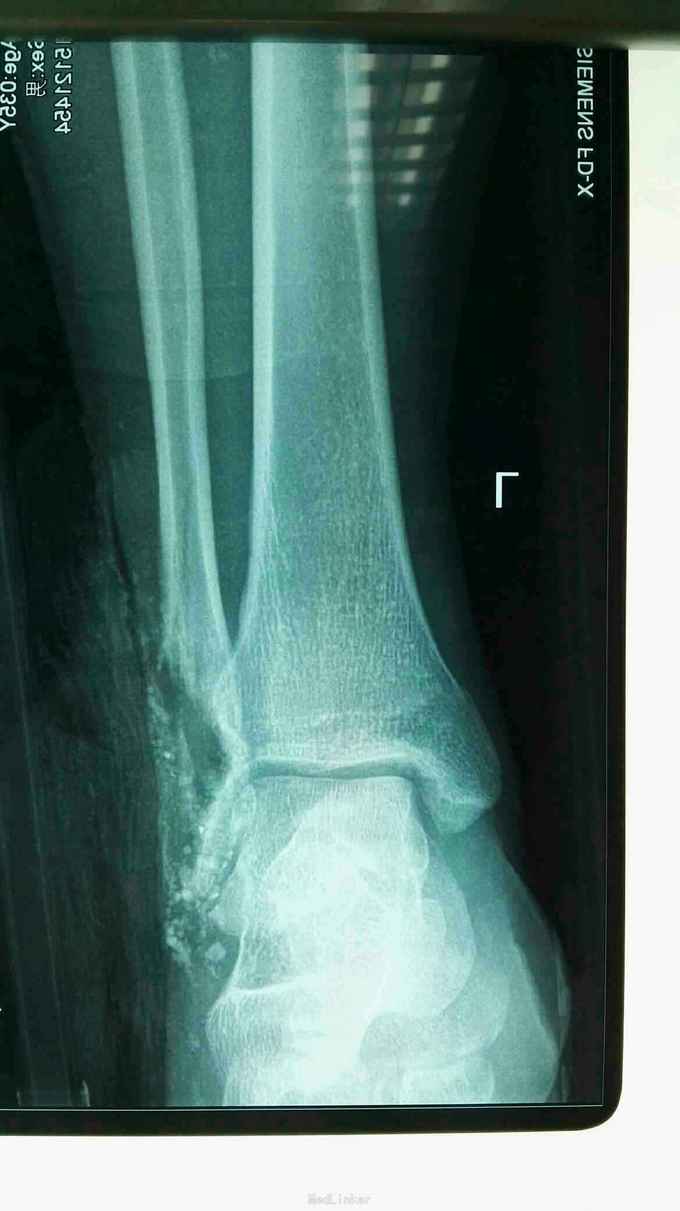

外踝毁损伤

患者男子,车祸致全身多次骨折,目前患者左外踝毁损伤,皮肤缺损约15*8cm,左外踝缺损长度5cm,目前一期手术给予清创+vsd负压吸引,给予局部冲洗。目前患者受伤第三天。术中情况见图。

左外踝入院时出院不止,伤口污染严重,血象高,d二聚体4500肝,肾功能正常

左外踝毁损伤